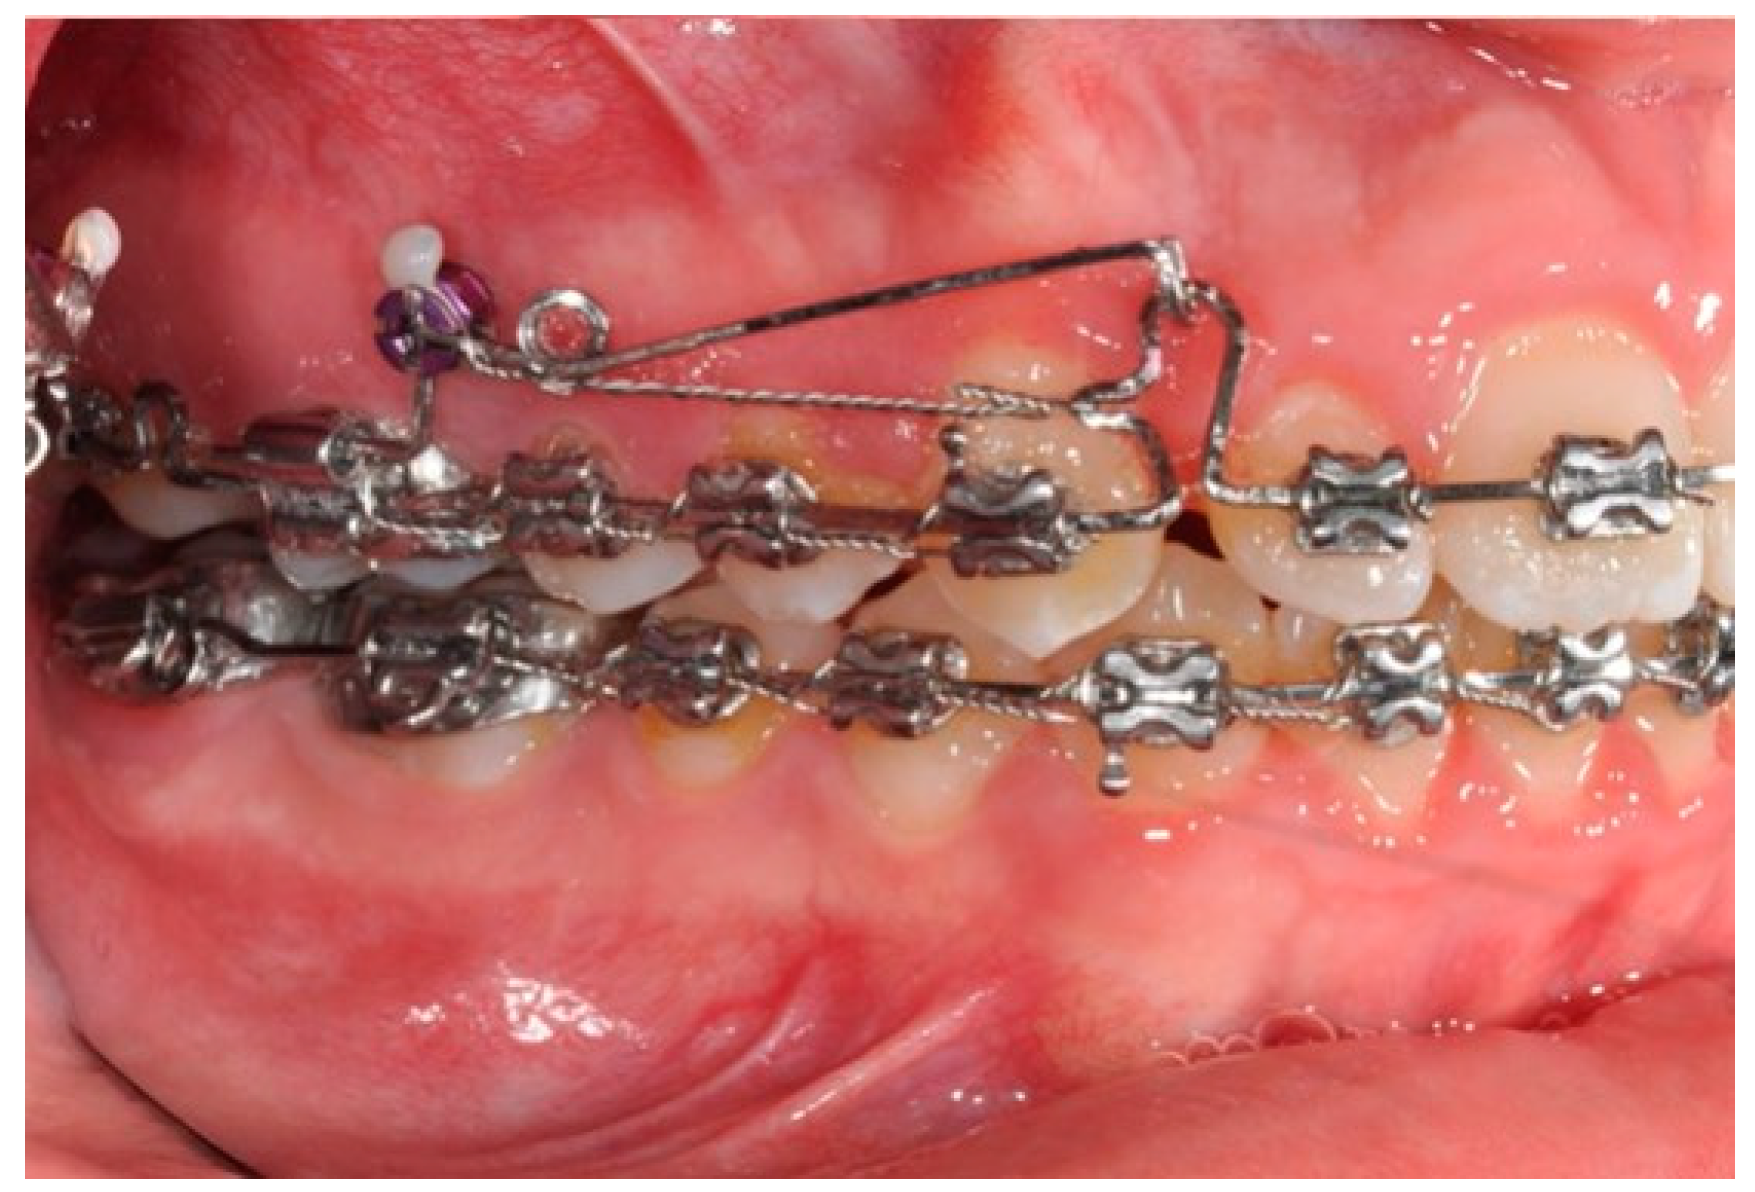

2.2. Molars’ and Premolars’ Distalization